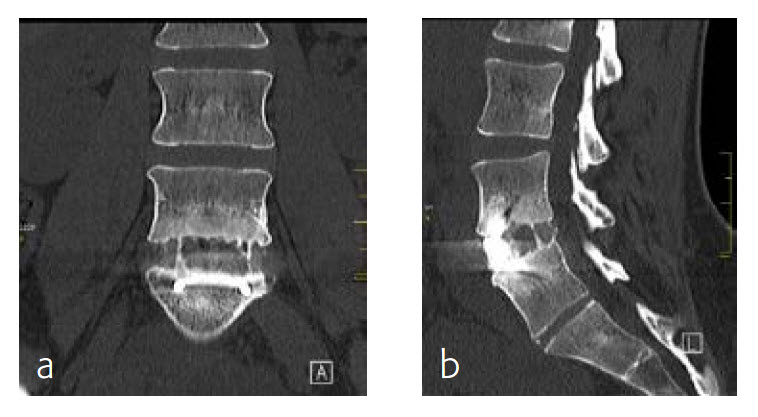

6-month follow-up

By the planned 6-month follow-up, the patient was pain free and fully active. Evaluation with CT scans was undertaken, consolidation was starting (Fig 8).